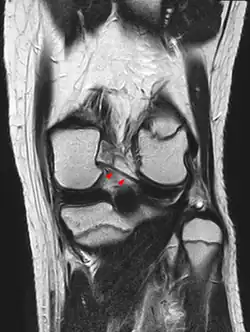

-

Posterior meniscofemoral ligament on MRI, sagittal -

Posterior meniscofemoral ligament (Wrisberg) behind the posterior horn of the lateral meniscus close to its insertion. Sometimes wrongly interpreted as a meniscal tear.